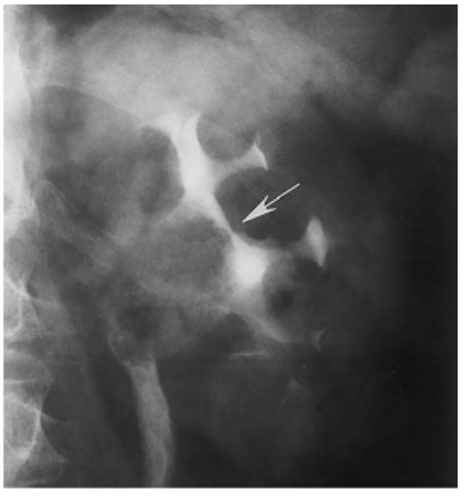

TCC in the renal sinus